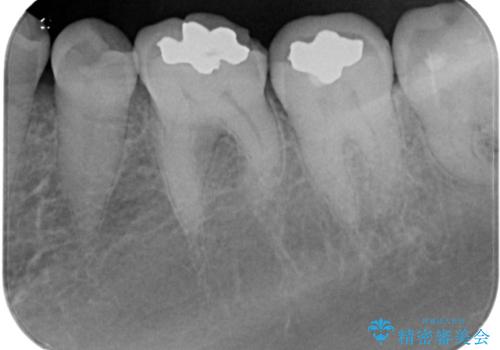

- 銀歯の周りに物が挟まるとのことで来院された患者様です。

咬合力が強く、銀歯周りの歯質に隙間が生じてむし歯になっている状態でした。

むし歯をしっかりと取り除き、強い咬合力を考慮してゴールドインレーにて修復することとしました。

ゴールドインレーは銀歯のインレーやセラミックインレーと比べ、「技工操作の精度が高く、適合が著しく良い」というメリットがあります。特に「適合の良さ」は再治療のリスクを防ぐ上でとても重要な要素となります。